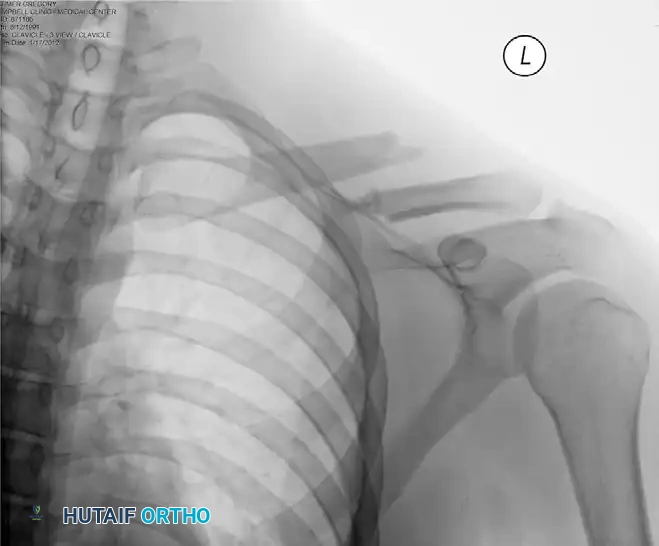

Preoperative radiograph demonstrating a significantly displaced midshaft clavicular fracture, an ideal candidate for surgical intervention.